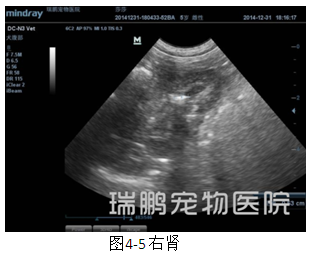

输尿管、膀胱切开取石术后3天,对患犬进行泌尿系统超声波检查,其结果显示膀胱内有尿液充盈,膀胱壁轻微增厚,凹凸不齐,未见明显的高回音性结石团块残留(图4-1);左肾盂仍然轻微扩张,肾脏长轴大小为3.92 cm(图4-2);肾门附近的输尿管通畅良好,管腔内未见明显异常的影像(图4-3);膀胱附近(原来输尿管结石部位)的输尿管通畅,无明显的异常影像(图4-4);右肾盂内仍然有高回音性影像,提示肾结石仍然存在,结石直径大小约为0.53 cm,肾脏皮髓质层交界模糊不清,肾脏轮廓不清晰(图4-5)。